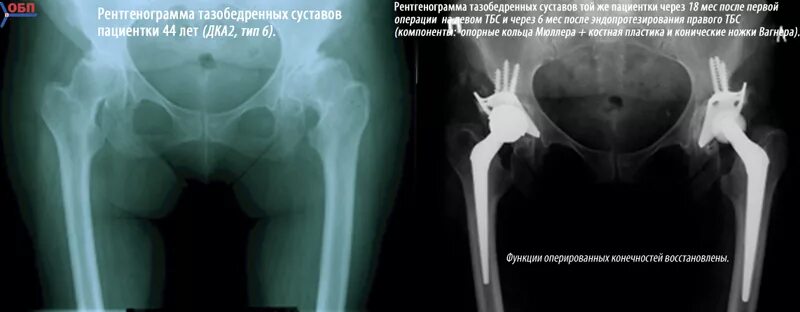

Рентген тазобедренный в двух проекциях